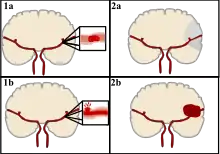

Strokes can be classified into two major categories: ischemic and hemorrhagic.[18] Ischemic strokes are caused by interruption of the blood supply to the brain, while hemorrhagic strokes result from the rupture of a blood vessel or an abnormal vascular structure. About 87% of strokes are ischemic, the rest being hemorrhagic. Bleeding can develop inside areas of ischemia, a condition known as "hemorrhagic transformation." It is unknown how many hemorrhagic strokes actually start as ischemic strokes.[2]

There are two main types of hemorrhagic stroke:[28][29]

- Intracerebral hemorrhage, which is basically bleeding within the brain itself (when an artery in the brain bursts, flooding the surrounding tissue with blood), due to either intraparenchymal hemorrhage (bleeding within the brain tissue) or intraventricular hemorrhage (bleeding within the brain's ventricular system).

- Subarachnoid hemorrhage, which is basically bleeding that occurs outside of the brain tissue but still within the skull, and precisely between the arachnoid mater and pia mater (the delicate innermost layer of the three layers of the meninges that surround the brain).